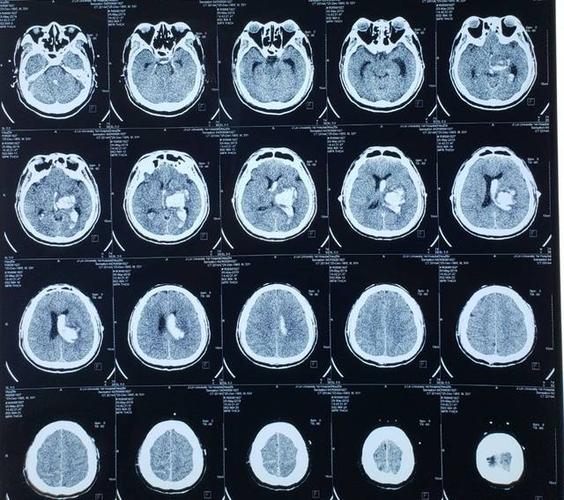

丘脑出血ct图片解说图

丘脑出血ct图片解说图,脑出血ct图片解说图

典型病例二: 左侧丘脑出血破入脑室系统

丘脑出血破入脑室

丘脑脑干急性出血激光定位紧急微创抢救一例

正文 回顾: 对于出血部位深的丘脑出血,选择微创穿刺

丘脑出血——内囊内侧型出血